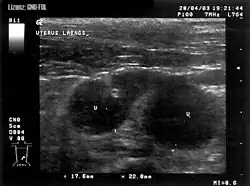

Pyometra beim Hund. Mit U gekennzeichnet sind zwei Uterusschlingen, welche vom Schallkegel quer angeschnitten wurden.